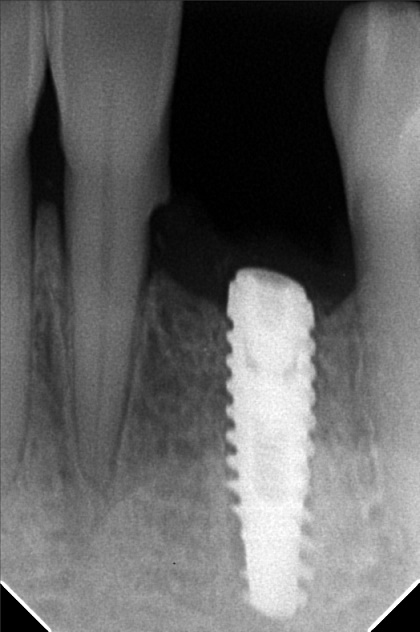

- Procedure

- img_20220622_140308.jpg

- george_escala_01.jpg